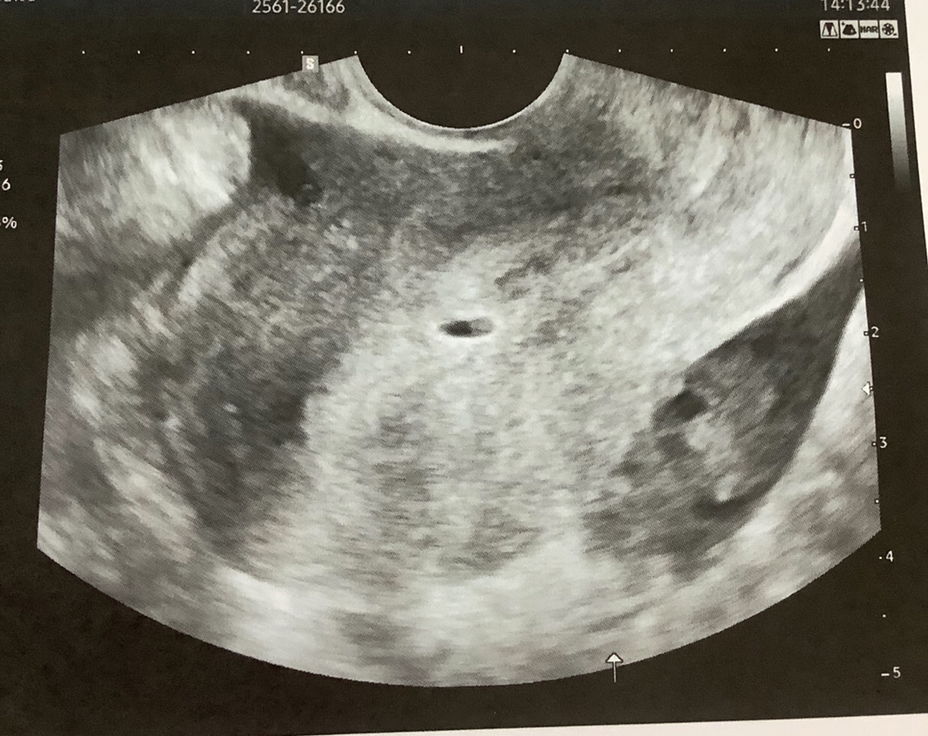

แท้ง 6 วีค ไม่มีสัญญาณเตือนอะไรเลยค่ะ

เมื่อวาน 4 ทุ่มนั่งอยู่ เลือดออกมาเยอะมาก ก่อนหน้าไม่มีอาการอะไรเลยค่ะ ปวดเสียดๆแป็ปเดียว เลือดออกเลย ไป รพ ใกล้บ้าน หมอซาวไม่เจออะไรเลย คอนเฟิมว่าแท้งจะให้ขูดมดลูกค่ะ เราขอกลับไปนอนก่อนเพราะถ้าขูดต้องลางานยาว บวกกับไม่ได้ปวดท้องมาก พอกลับมานอนตอนเช้าเลือดออกเหมือนเป็นเมน ทำใจแล้วว่าน้องคงไม่อยู่แล้ว วันนี้เลยไป รพ ที่ฝากครรภ์ ปรากฎว่าซาวเจอถุงค่ะ แต่เล็กมาก มีไข่แดงอยู่ข้างใน หมอบอกว่าเลือดออกเยอะแล้ว น้องคงพัฒนาต่อไม่ได้เดี๋ยวคงหลุดออกมาเอง เราก็ยังหวังแต่กลับบ้านมาพยามนอนแต่เลือดก็ออกเยอะมากค่ะ คงทำใจแล้ว หมอนัดดูอาการอีกรอบ คาดว่าถุงน่าจะหลุดในสองสามวันนี้ค่ะ เสียใจมาก อาจจะเพราะช่วงท้องวีคแรกๆเราเครียดด้วยค่ะ